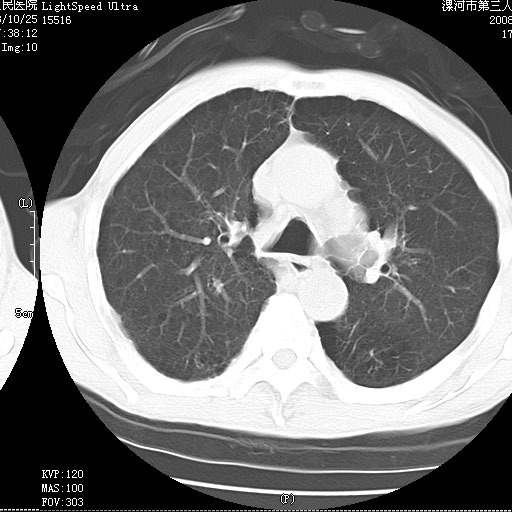

m 老年 发烧、呼吸困难,慢支、肺气肿多年;记的那次是下午大概17:38做的,晚上窒息死亡。

上面的层面就慢性支气管炎肺气肿、肺大泡,别的没有什么、也就不传了。

当时我怀疑:1、阻塞性肺不张早期 2、肺脓肿早期,望老师们发表意见